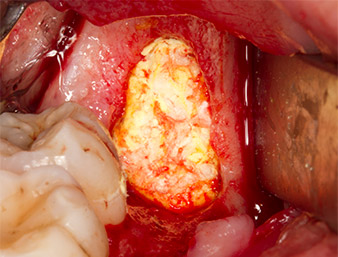

Pour obtenir un matériau autogène en vue du traitement ultérieur de la plaie, des fragments osseux sains sont collectés autour du reste radiculaire à l'aide d’un insert piézochirurgical (Piezomed B5) (Fig. 5).

Le tissu autogène est extrait à l’aide de la section en forme de racloir de la pièce active de l’insert et conservé dans un soluté physiologique isotonique jusqu’à utilisation ultérieure (cf. Fig. 13).

Puis le tissu osseux autogène (Fig. 13) est placé dans l’alvéole et le défaut osseux voisin (Fig. 14). Une membrane de collagène recouvre les fragments osseux à hauteur de l’os afin de protéger le nerf exposé (Fig. 15). Pour refermer le tissu mou ouvert, on utilise du fil de suture Vicryl, USP 4.0 (Fig. 16). Une préparation à base d’ibuprofène (Seractil 400 mg, 3x1) et un antibiotique associant amoxicilline et acide clavulanique (Augmentin 1 g, 2x1) sont prescrits en postopératoire.